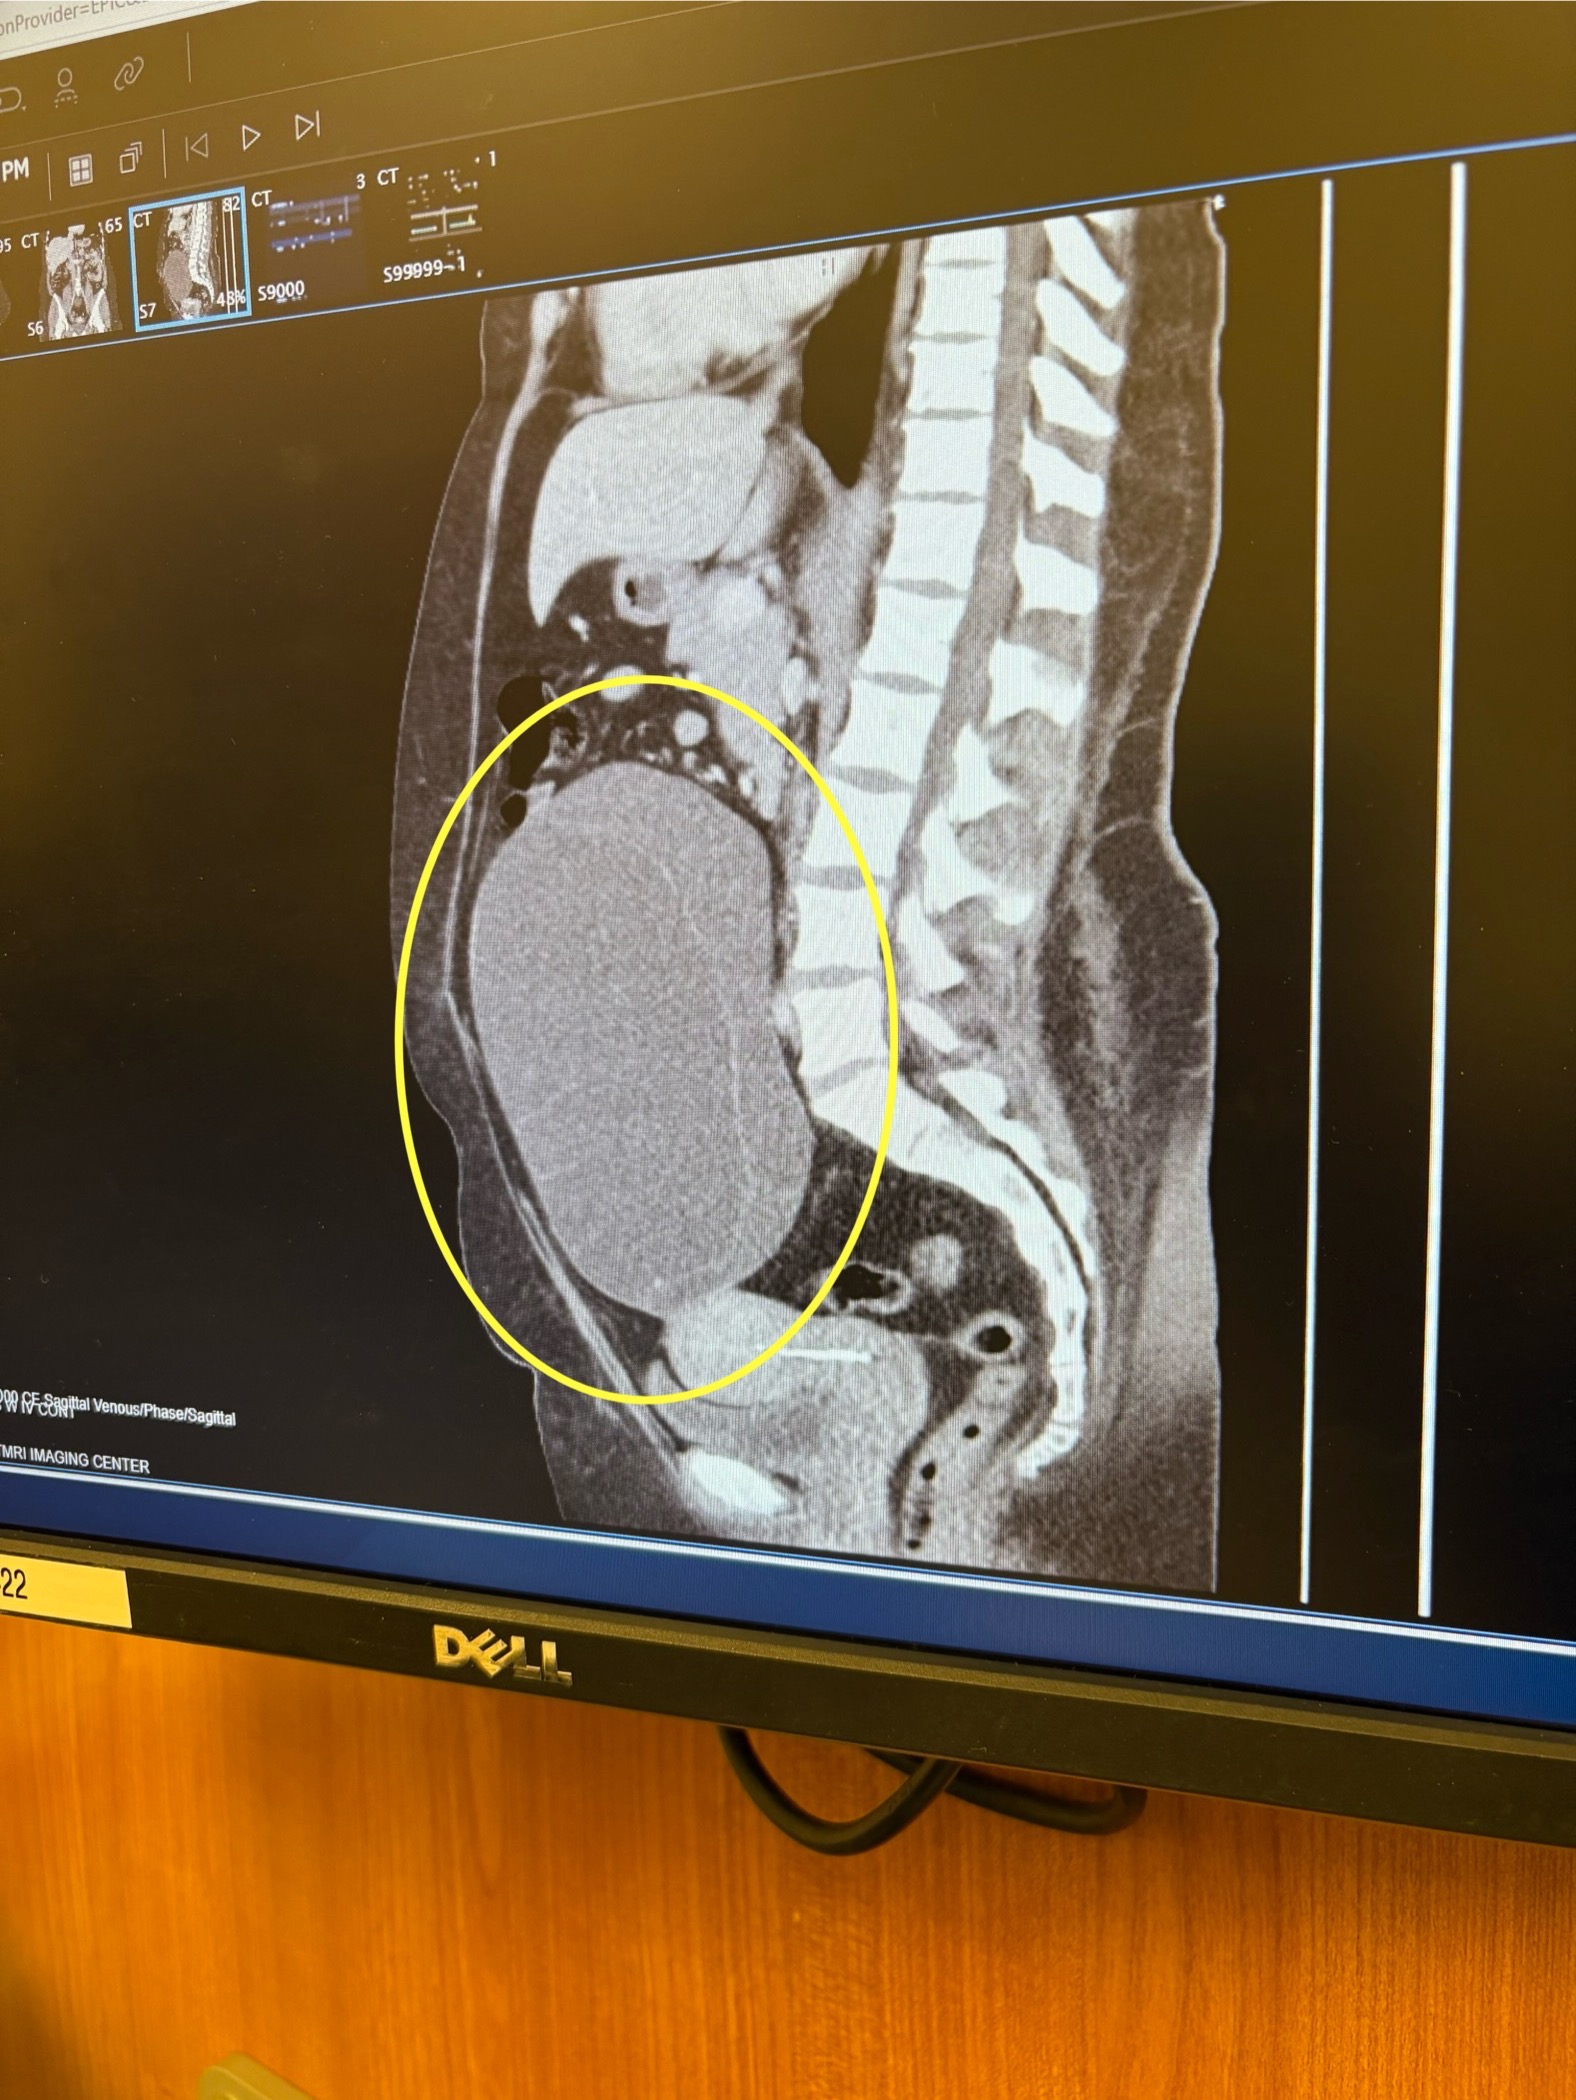

Things again seemed to be going alright again until April 22nd 2025 when I had a CT scan done and the doctor’s found a 8.5 inch ovarian cyst. Thankfully, it’s not cancerous. I had to get an MRI and schedule surgery. I’m already in my head and distraught, when I get into another car accident. Now I’m dealing with insurance again, all the while working myself up over my surgery and how I’m going to afford all my bills since I won’t be working for two weeks while I recover.